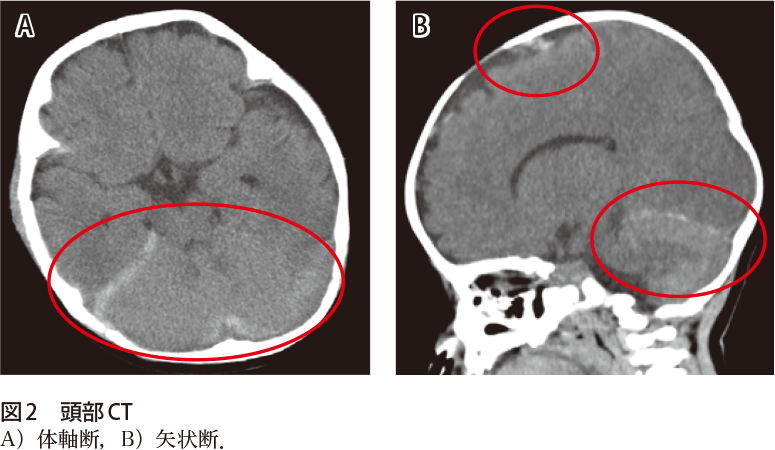

解答 解説 けいれん 意識障害で搬送された5カ月女児 実践 画像診断q A 羊土社 レジデントノート 羊土社

慢性硬膜下血腫 地方独立行政法人大阪府立病院機構 大阪急性期 総合医療センター

慢性硬膜下血腫

慢性硬膜下血腫 対象疾患 医療関係者へ 近畿大学医学部 脳神経外科

慢性硬膜下血腫 対応疾患 流山中央病院 脳神経外科ホームページです 日本脳神経血管内治療学会研修施設 認定病院 脳動脈瘤 クモ膜下 出血 脳出血 脳梗塞などの血管障害だけでなく 脳動静脈奇形や硬膜動静脈瘻といった 珍しい疾患もカバーしています